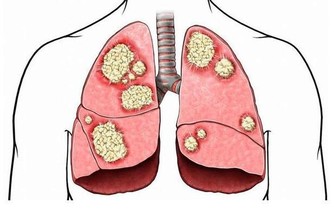

特別藥物:須飲水2000毫升以上為削弱特別藥物毒性,避免對器官特殊是對腎贓的損傷,請求服用藥物後每日必需飲水2000毫升以上。比如:在服用抗痛風藥後,應大批飲水,以下降黃嘌呤結石以及腎內尿酸沉積的風險;服用排尿結石的藥後,也需大批飲水,以沖刷尿道、稀釋尿液,從而下降尿液中鹽類的濃度和尿鹽沉澱的機遇。